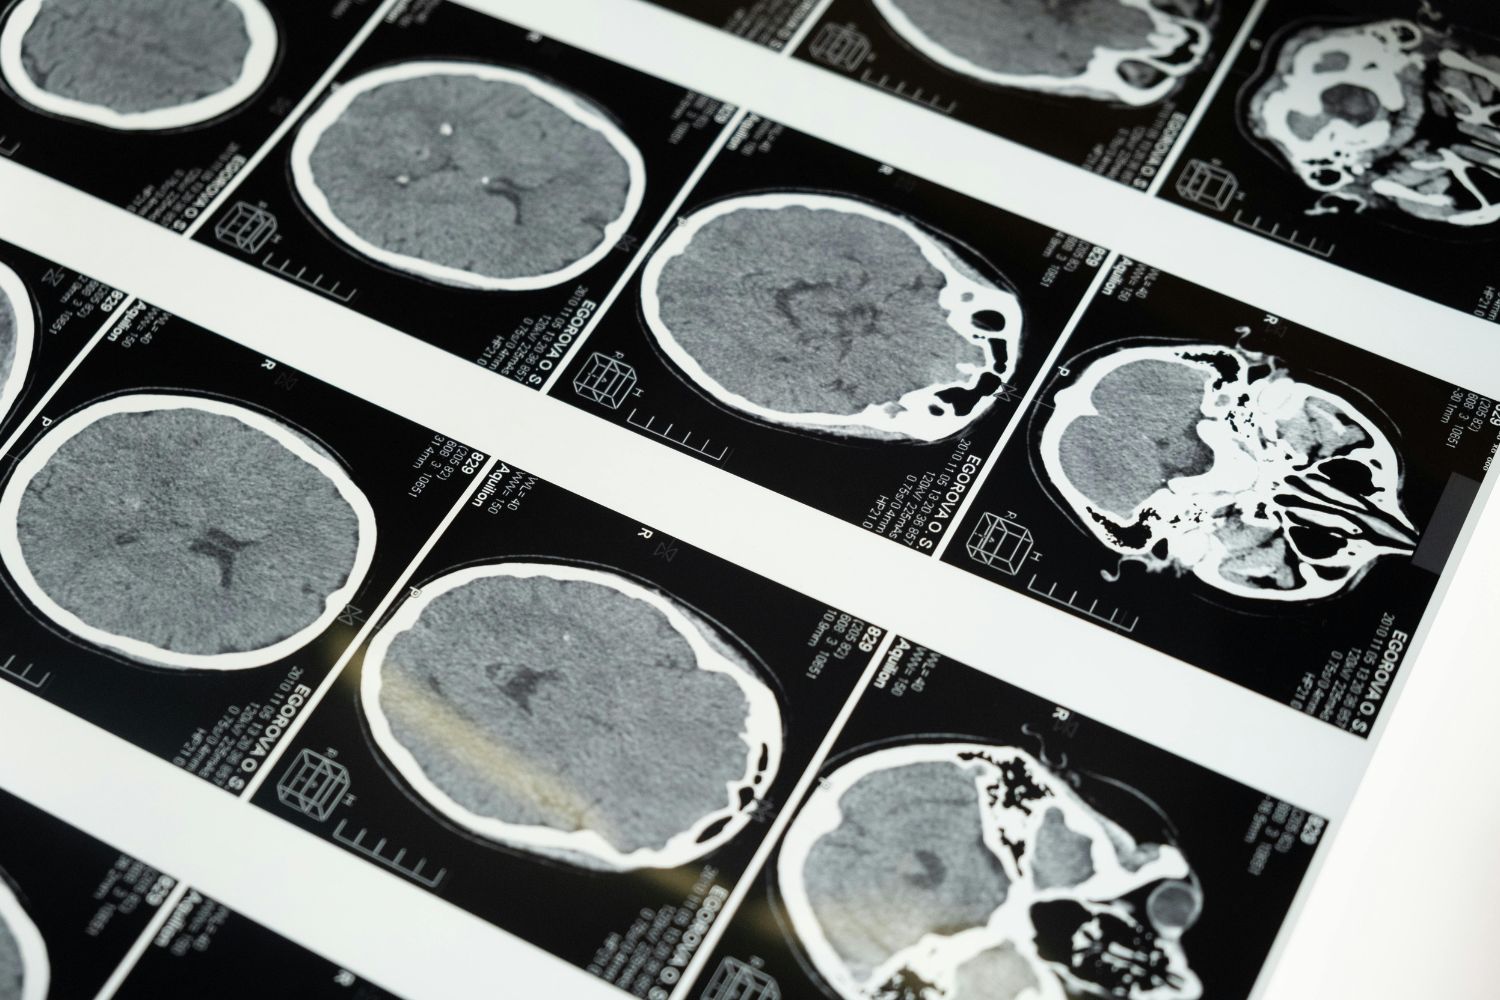

La estenosis carotídea es una afección provocada por la acumulación de placa en las arterias carótidas, responsables de llevar sangre rica en oxígeno al cerebro. El principal peligro aparece cuando un fragmento de esa placa se desprende y bloquea el flujo sanguíneo, desencadenando un accidente cerebrovascular.

Los investigadores analizaron la aparición de accidentes cerebrovasculares y fallecimientos en las semanas posteriores a los procedimientos, así como el riesgo de ACV a lo largo de cuatro años en el lado del cuerpo irrigado por la arteria afectada.

El equipo de investigación continuará monitoreando a los participantes para evaluar los resultados a más largo plazo. Además, se están explorando nuevas herramientas de diagnóstico por imágenes que permitan identificar con mayor precisión qué pacientes se benefician más de cada estrategia.